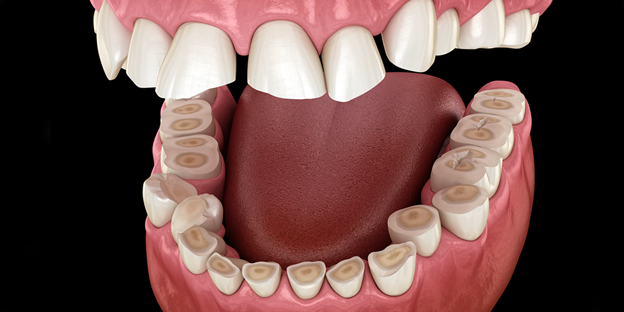

- ✨ Thói quen nghiến răng (Bruxism) khi ngủ

- Nghiến răng kéo dài gây mài mòn men răng, suy yếu cấu trúc răng. Khi kết hợp với vệ sinh răng miệng kém, nguy cơ viêm tủy răng tăng cao, răng trở nên nhạy cảm, đau nhức và dễ bị tổn thương lâu dài.

Các giai đoạn viêm tủy răng cần lưu ý

- 🔹 Viêm tủy có phục hồi

- Đây là giai đoạn đầu của viêm tủy, thường khó nhận biết do triệu chứng chưa rõ ràng.

- Biểu hiện thường gặp: đau từng cơn, ê buốt nhẹ, kéo dài về đêm hoặc khi ăn đồ quá nóng/lạnh.

- Giai đoạn này rất ngắn và dễ nhầm lẫn với các bệnh lý răng miệng khác.